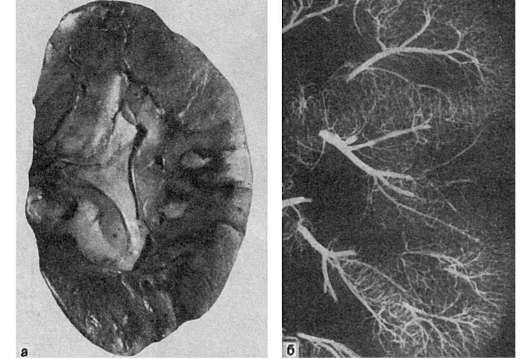

Рис.

47. Инфаркт почки:

а - белый инфаркт почки с геморрагическим венчиком (вид на разрезе); б - ангиорентгенограмма той же почки. Отсутствие сосудов в области инфаркта